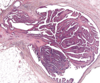

what is the histologic appearance of cribriform non-comedo ductal carcinoma in-situ

rounded (cookie cutter like) spaces filled with calcified material

a rounded, cookie cutter link appearance histologically is indicative of what

cribriform non-comedo ductal carcinoma in situ